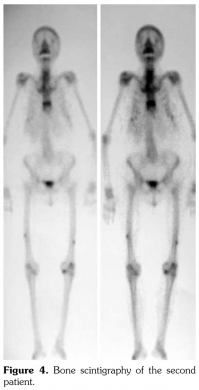

Case 2– A 61-year-old female patient presented with anterior thigh pain and difficulty in walking. Pain severity was 7 over 10 point according to visual analog scale. She had been treated with alendronate 70 mg per week with calcium plus vitamin D for two years. Plain radiographs of femur were taken upon clinical presentation. Cortical stress reaction was detected in both femoral shafts on plain radiographs (Figure 2). Computed tomographic imaging was performed to rule out fracture (Figure 3). Bone scintigraphy showed increased uptake in distal (1)/3 ends of femoral shafts (Figure 4). Serum calcium value was normal and urinary deoxypiridinoline level was mildly increased (46 nM/mMCre).

Bone scintigraphy of the patients revealed increased uptake in femoral diaphysis. Atypical bisphosphonate associated subtrochanteric and femoral shaft stress fractures show specific appearance on bone scintigraphy characterized by mild uptake in multifocal endosteal thickening of the lateral femoral diaphysis.(11)